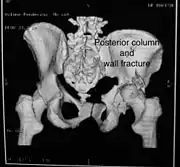

Posterior column and wall fracture as seen on 3D CT

Posterior column and wall fixed using screws and plates

| Posterior column | As with posterior wall injury, this also typically occurs due to dash board injury. | Posterior column + Posterior wall | These fractures are extensions of elementary fractures. With the involvement of the posterior wall, the difficulty in treatment increases. These fractures are rarely amenable to non-surgical treatment. Due to posterior wall fracture, the hip is usually dislocated posteriorly, requiring immediate reduction of dislocation and surgical reconstruction after a few days.

The posterior column with posterior wall fracture occurs due to dashboard injury. The anteroposterior view may give clues to these injuries. Judet views and CT scans help in knowing the extent of the injury. |